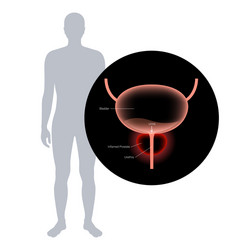

- Urinary

- Enlarged

- Prostate

- Bladder

- Body

- Anatomy

- Disease

- Disorder

- Health

- Human